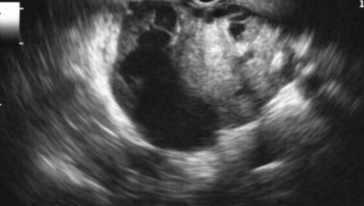

Describe this image

Dx?

An EUS image of a well-defined, hypoechoic cyst with a “central star” and microcysts/septations.

Dx: benign serous cystadenoma